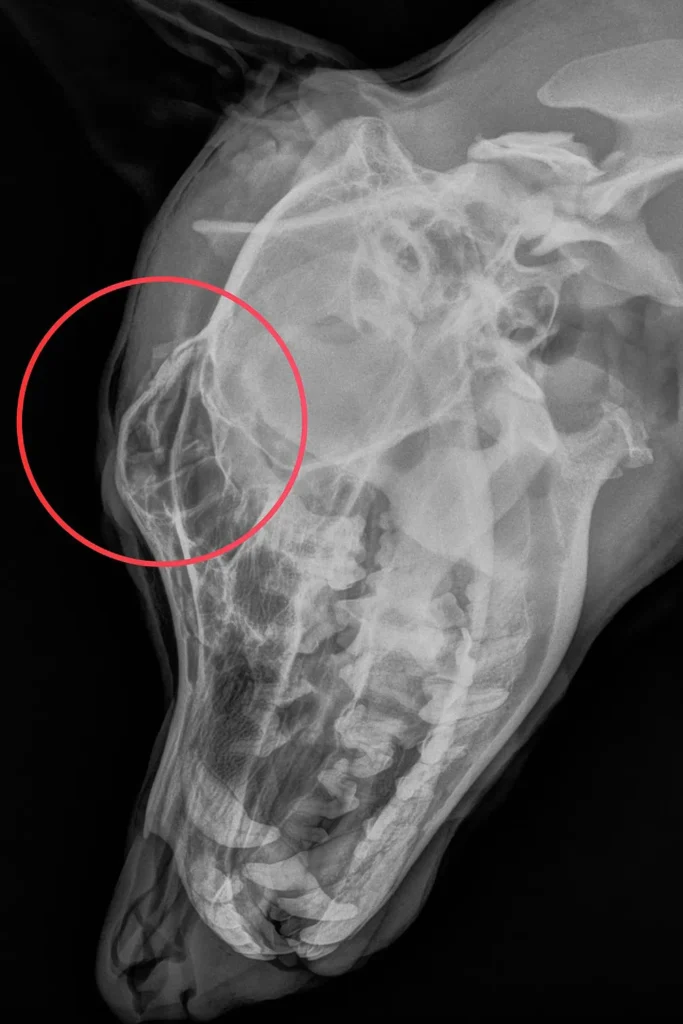

Justice’s condition became even more heartbreaking once she was examined by veterinary professionals. After being transferred into the care of the Pennsylvania SPCA, medical staff discovered she had suffered a skull fracture—an injury they believe was intentionally inflicted.

Rescuers did not hold back in describing her state. “Tethered. Beaten. Broken—but not beyond hope,” the organization said, capturing both the brutality she endured and the fragile optimism surrounding her recovery. The phrase has since become symbolic of her fight to survive.